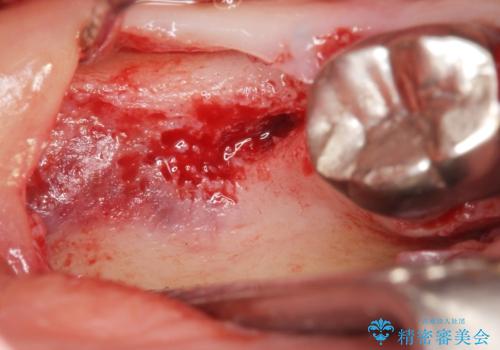

骨が少なく下顎神経に近いことから、他院でインプラントできないと言われたとのことでした。

骨増生(GBR)を行い骨を増やすことでインプラント治療を可能にしました。